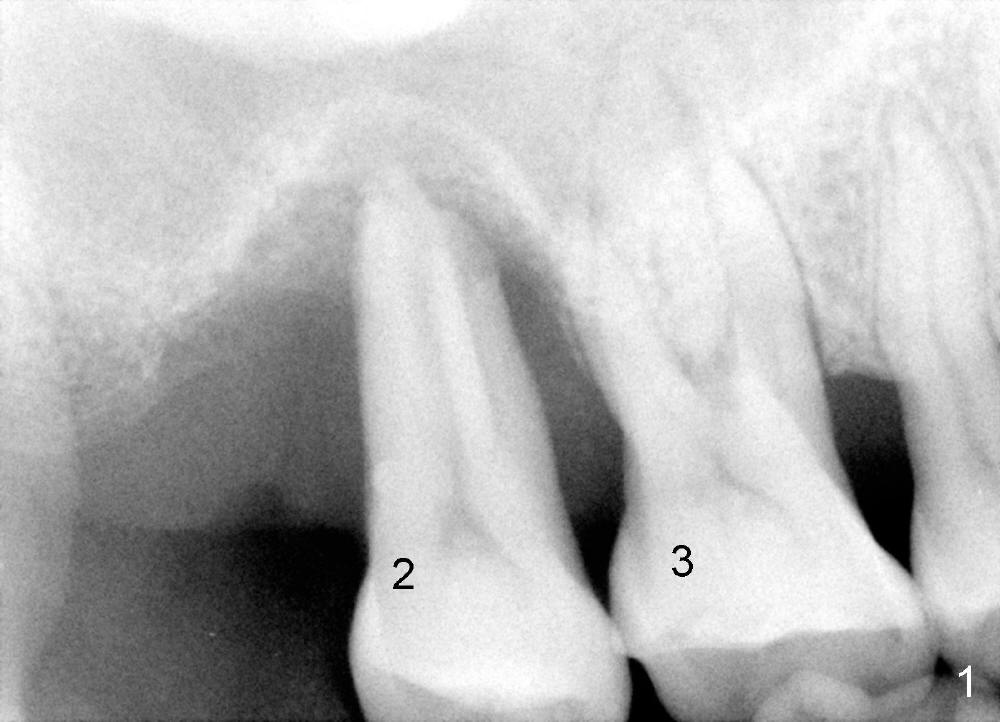

50岁男士有严重牙周炎(图一(2009年拍摄):二号牙(左上七)最终拔除(与图二对比)),最近三号牙(左上六)冷热痛,而且不能咬东西,三号牙多处牙周袋深,根尖片显示远中颊侧和腭侧根尖阴影(图二箭头),初步诊断:牙周牙髓综合症,需要根管治疗以及牙周手术,还可能保留不了。开髓表明活髓,近中颊侧和远中颊侧(DB)根管口很接近(参考图一图二),扩大(30/.04)后并表现不出来(图五至图七),开始近中根管口好像比较接近腭侧根管口,以为是MB2,使用Piezo超声波/diamond tip在MB(图六*)颊侧和近中寻找另外一个根管(箭头),但不成功。腭侧根管扩大到40/.06,匆匆忙忙插入主牙胶尖,拍摄根尖片(图三),显示远中颊侧以及腭侧(P)牙胶尖在相应牙根正中,但是近中颊侧并不是这样(图四=图三+MB牙根和牙胶尖轮廓),这说明还存在另外一个根管。经过再次合适扩大(crown down),腭侧牙胶尖进入更深地方(临床上),这时病人已经坐立不安了,paper points吸干根管后,拍摄图五至图七,暂封。由于病人还缺失好几颗牙齿,劝他去拍摄CT。今天术后第五六天,打电话给他,他很高兴,说冷热痛消失,牙齿也牢靠多了,但是还没去拍摄CT。下周三他回来完成根管治疗。

如果他还没有CT,我该怎么在没有外科显微镜下找遗留根管呢?MB和P根管口之间的确有一个沟(map),但是非常光滑(图五至图七),能找到根管口?还是往原来MB根管口颊侧探索?图三/图四暗示MB1还没有被发掘,对吗?MB2存在吗?